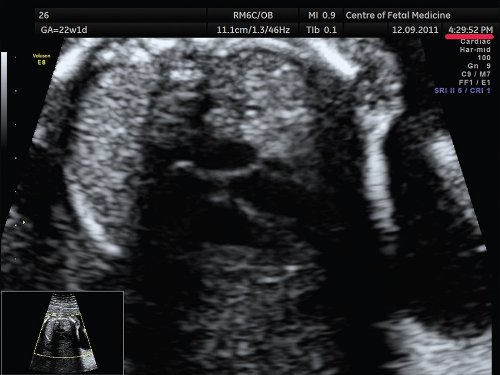

Наиболее распространенной и грубой ошибкой является оценка сердца плода в общем акушерском режиме. Почему так важно производить осмотр сердца плода в специальном режиме и какие принципиальные отличия данного режима от общего акушерского? Необходимо помнить, что сердце плода - это орган, который находится в постоянном движении, причем систола, диастола, движения клапанов происходят в 2 раза быстрее, чем в сердце взрослого человека. Чтобы получить более четкое ультразвуковое изображение движущегося органа, необходима высокая частота смены кадров. Частота смены кадров зависит от частоты датчика, которым производится осмотр, а также от угла развертки ультразвукового изображения. При использовании общего акушерского режима угол развертки изображения по умолчанию установлен на 60-65°, достигаемая при этом частота смены кадров является вполне достаточной для получения четкого изображения при осмотре большинства органов плода. Грудная клетка и сердце плода во II триместре беременности имеют небольшие размеры, для их визуализации вполне достаточно проводить сканирование при угле развертки изображения, равном 30°. При этом частота смены кадров увеличивается более чем в 2 раза. Примеры изображения сердца плода при использовании акушерского и сердечного режимов с различными углами развертки представлены на рис. 1.

а) Эхограмма получена при сканировании в общем акушерском режиме. Обращает на себя внимание более широкий угол развертки изображения, контуры структур сердца более утолщенные и нечеткие по сравнению с изображением сердца в специальном сердечном режиме с узким углом развертки изображения.

б) Эхограмма получена при сканировании в сердечном режиме. Контуры структур сердца более четкие, изображение более контрастное, по сравнению с изображением сердца на рис. 1a.